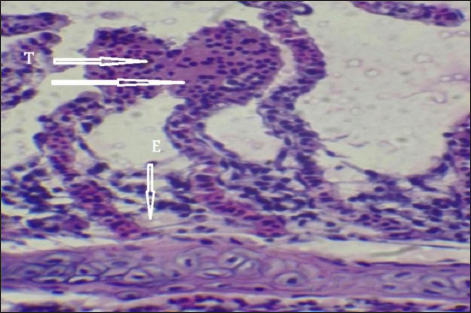

Histopathological findings of gill section showed telangictatisis and epithelial lifting in secondary lamellae (Fig. 7) with hemorrhage and blood congestion (Fig. 8), also, the result showed the central venous dilation with blood congestion and epithelium hyperplasia with complete fusion of the secondary lamellae (Figs. 9 and 10) and edema in the filamentary epithelium (Fig. 11) in addition to mononuclear cells infiltration (Figs. 12 and 13).

Fig. 11. Histopathological sections of gill of C. carpio showing edema in the filamentary epithelium (E) (H&E X40).

The changes in gill tissue are not exclusive to As, Pb, and Hg toxicity (e.g., telangiectasis, epithelial lifting, hemorrhage, congestion, etc.) which have been previously reported in other stressful situations, like pesticide exposure (Fanta et al., 2003). All of these changes may be defense mechanisms meant to lengthen the time it takes for waterborne contaminants to diffuse and enter the bloodstream (Arellano et al., 1999). With particular reference to exposure to metals, Mustafa et al. (2012) observed telangiectasis, necrosis, in mirror carp C. carpio exposed to Cu, with the epithelium lifted away from the basement membrane. Similar results were also noted in Sole senegalensis, the Senegalese sole, after it was exposed to a sub-lethal concentration of Cu for 7 days (Arellano et al., 1999).